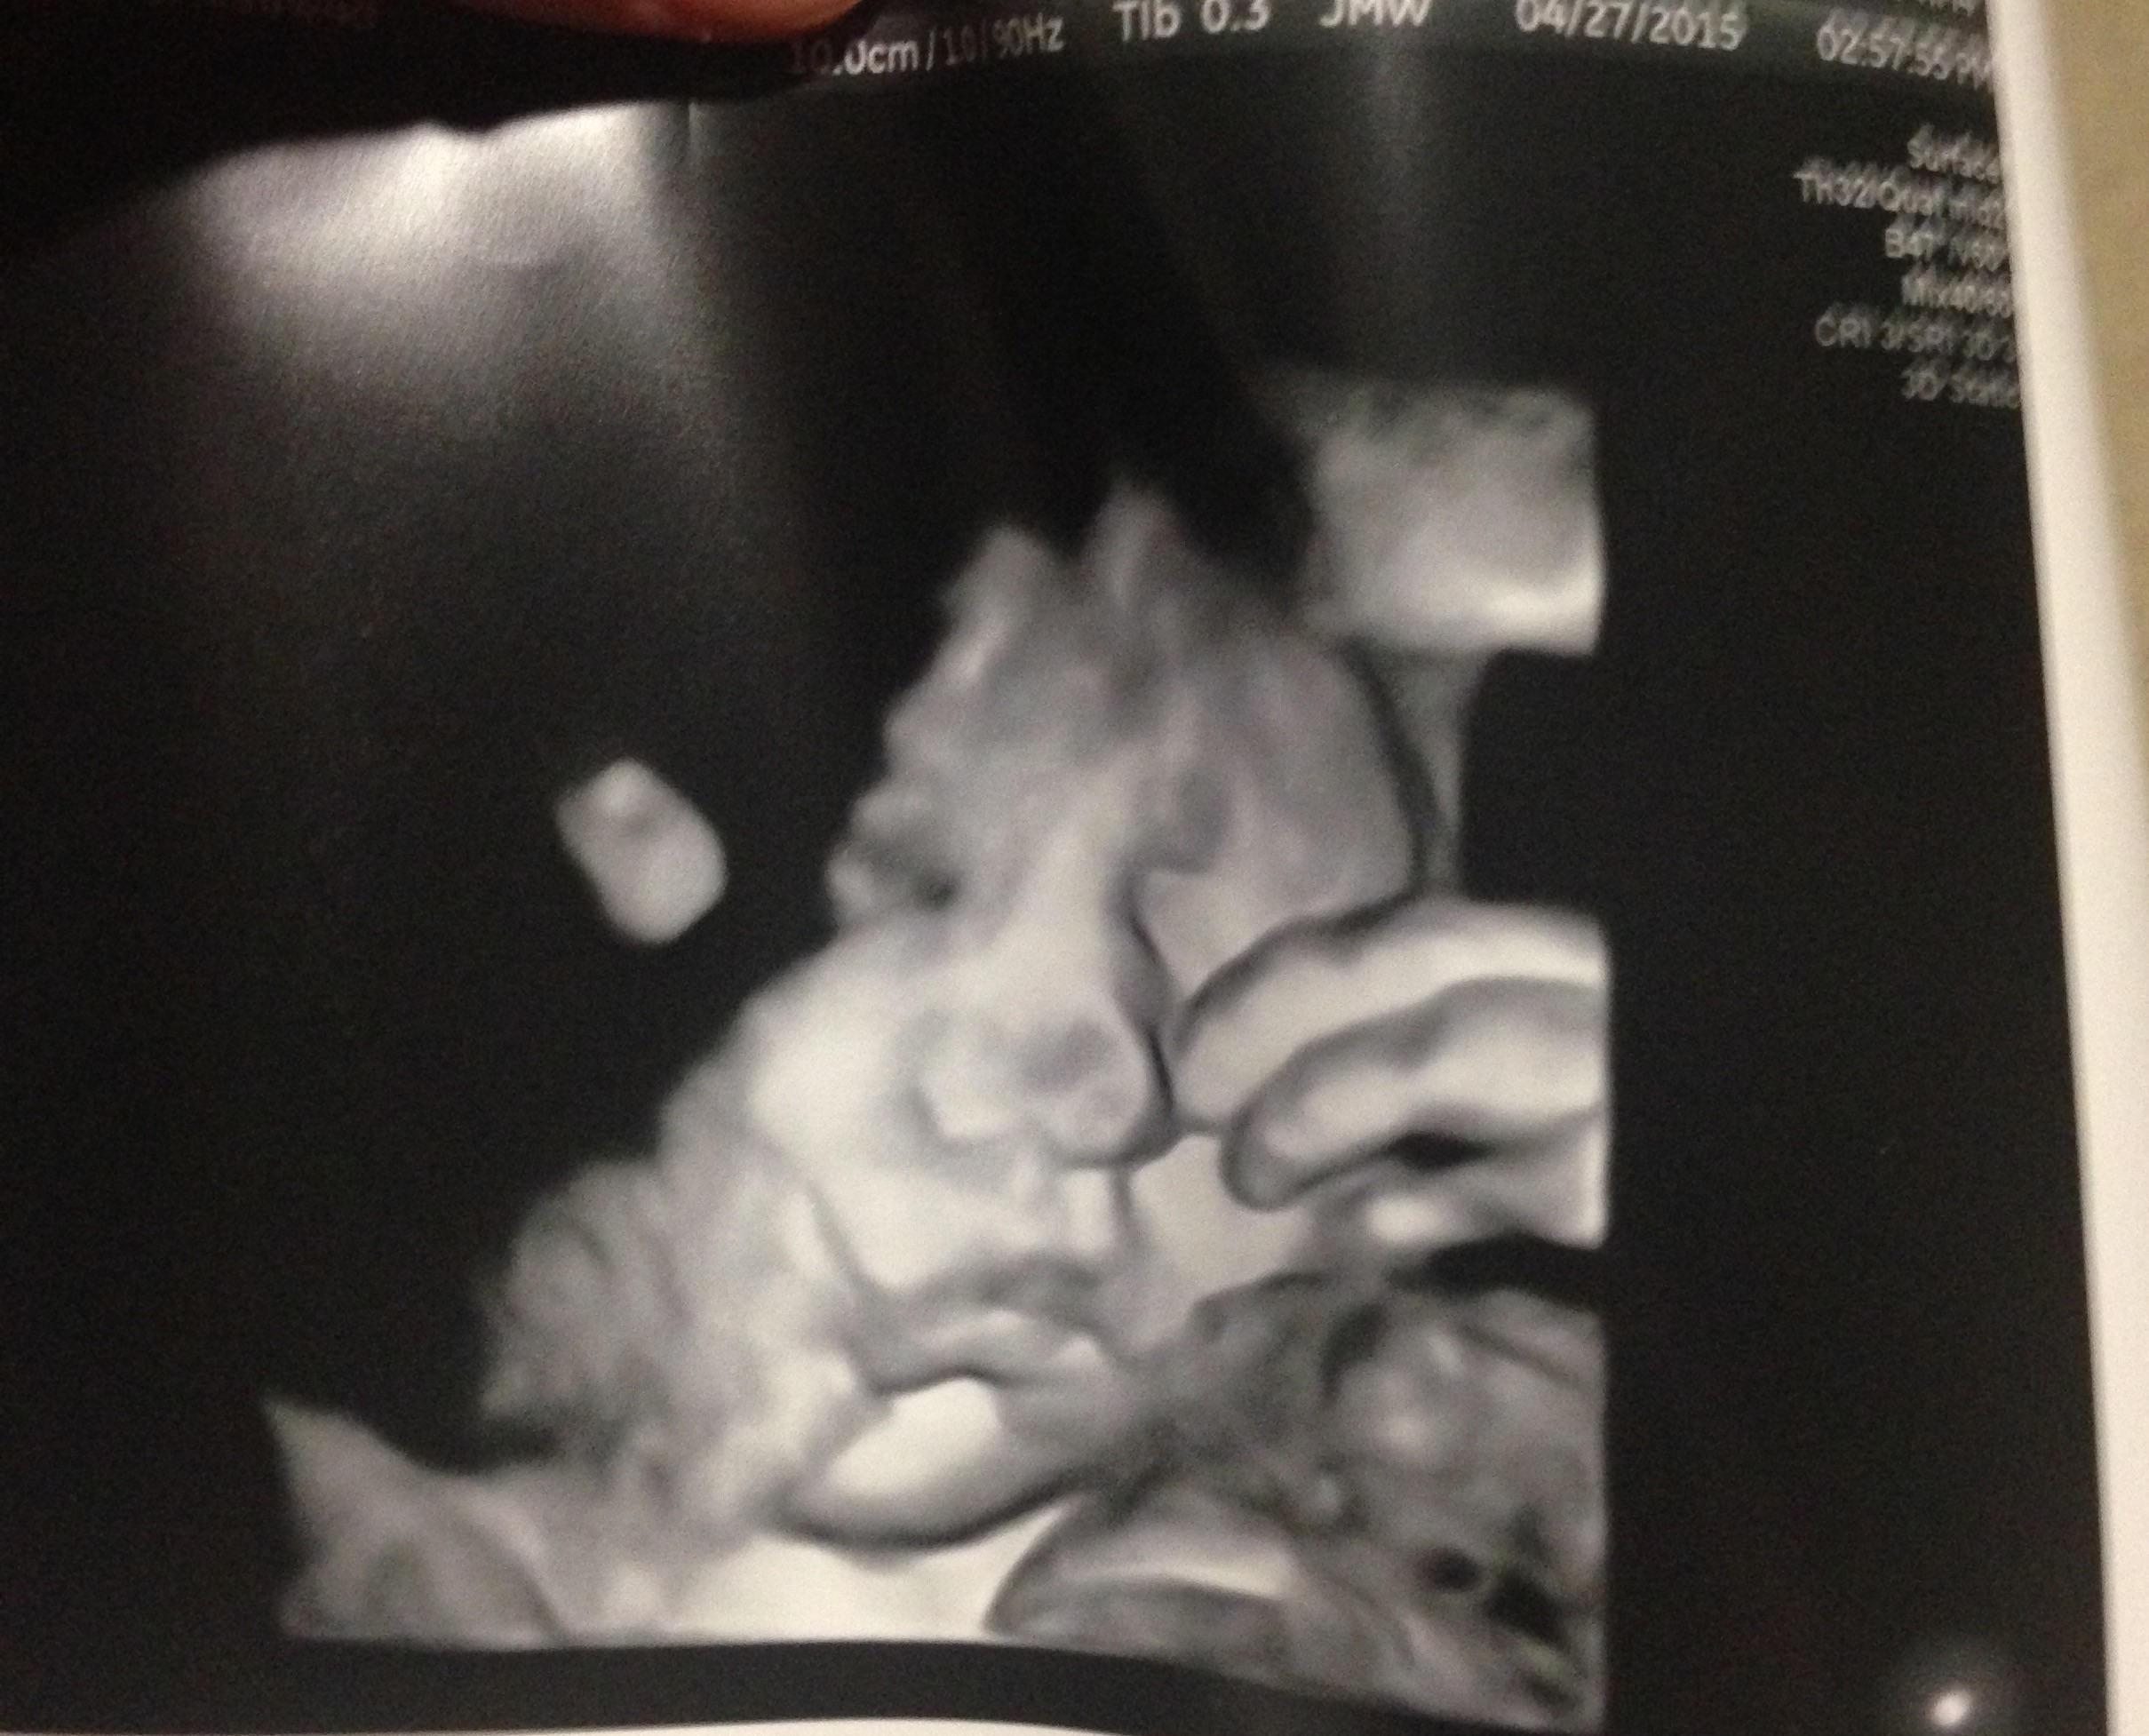

We did an early ultrasound to find out the sex of the baby at 17 weeks. I had strawberry oatmeal for breakfast and my husband and I headed to the appointment. Not only did our baby actually look like a baby, compared to our 12 week ultrasound, but we also got to see her swallowing the amniotic fluid and yawn on the u/s. It was one of the neatest things to see and it really made me realize that there was a living being in there taking over my body lol.

Our anatomy scan when LO was sucking on her hand. Also, at our ultrasound with the high risk specialist she had her elbow covering her eyes...like cmon I'm trying to sleep here.